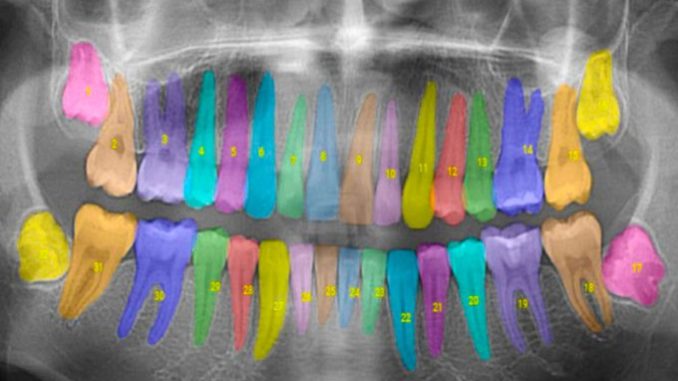

Inam is the co-founder of Overjet, a company using artificial intelligence to analyze and annotate X-rays for dentists and insurance providers. Overjet seeks to take the subjectivity out of X-ray interpretations to improve patient care.